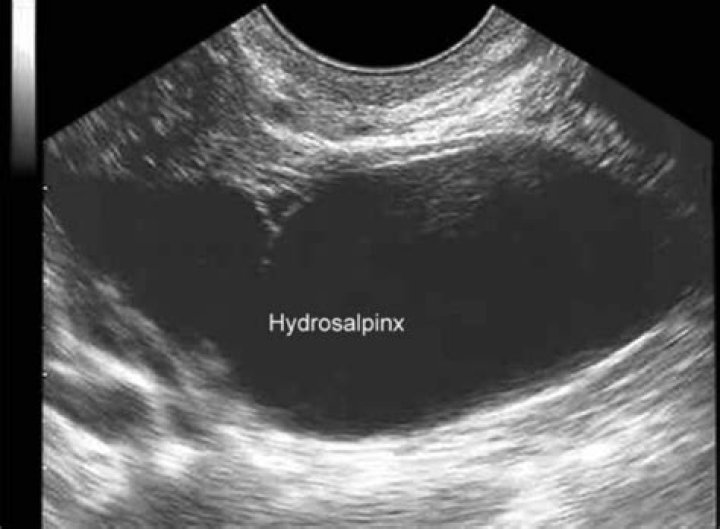

Can you see Hydrosalpinx on ultrasound?

Your doctor may be able to detect the presence of a hydrosalpinx on ultrasound. If your tube appears enlarged on ultrasound, this usually indicates a more severe hydrosalpinx. Your doctor will make a small opening in your belly and insert a special telescope or laparoscope to look at your uterus and fallopian tubes.

Hydrosalpinx is the condition in which the end portion of a woman's fallopian tube becomes fluid-filled and swollen, which can cause infertility.